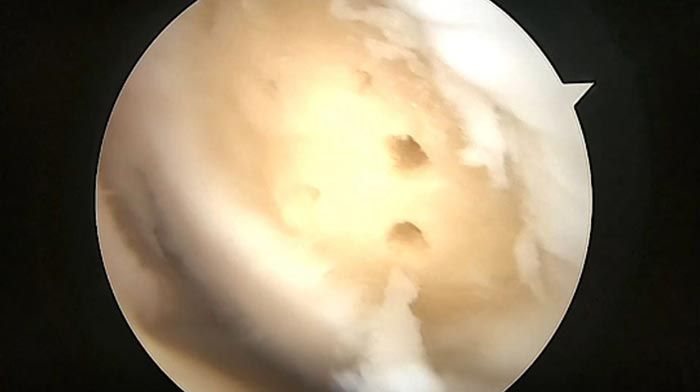

fracturas complejas, lesiones deportivas, cirugía de meniscos, de ligamento cruzado anterior, de ligamento cruzado posterior, cirugía de preservación del cartílago articular y reemplazos totales de las articulaciones hombro, cadera y rodilla.

cirugía de mínima invasión

ARTROUPN - Artroscopía de hombro

ButtonARTROUPN - Ligamentos cruzados

ButtonARTROUPN - Preservación de cartilago

ButtonARTROUPN - Cirugías de mínima invasión

ButtonARTROUPN - Trasplante de menisco